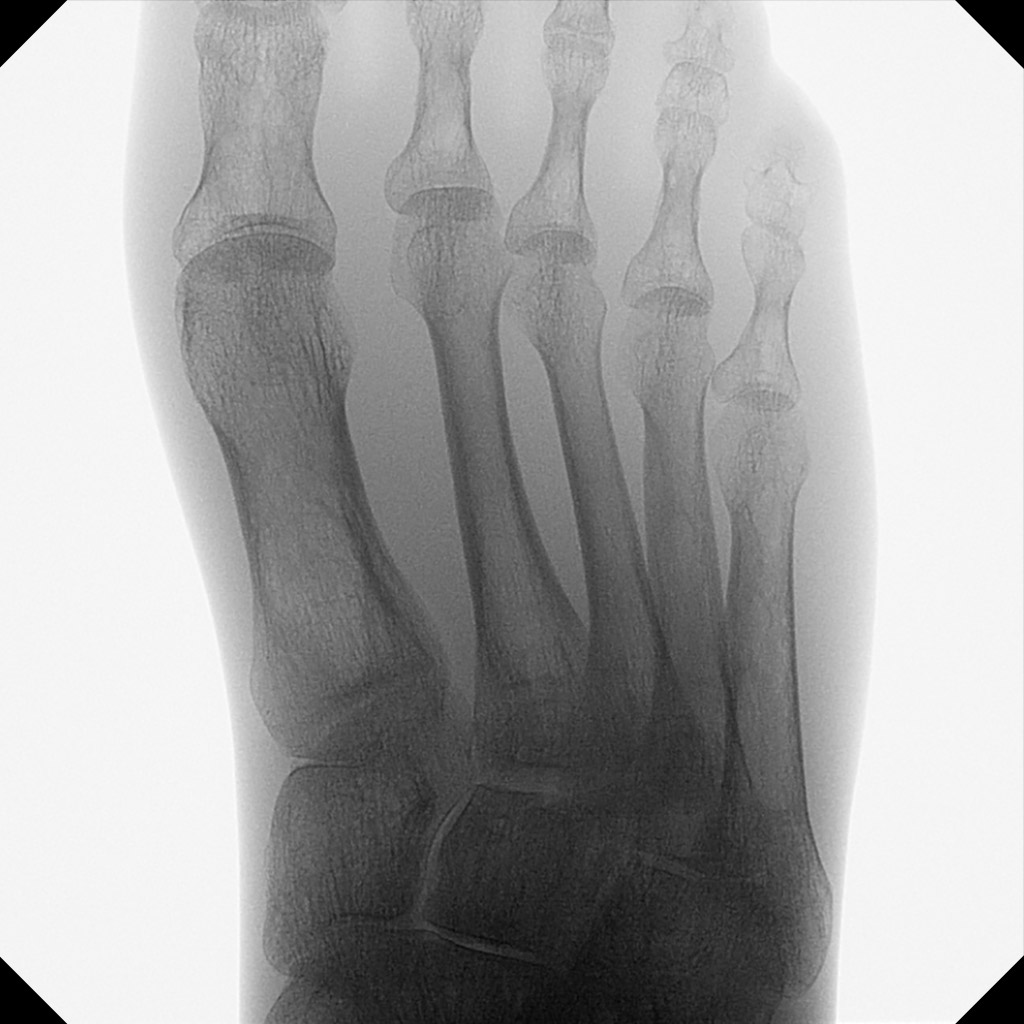

Les mini arceaux chirurgicaux améliorent considérablement la prise en charge des patients pour la chirurgie de la main et du pied.

Orthoscan propose dans ce domaine un portefeuille complet d’appareils avec fluoroscopie pulsée et capteurs plans ultramodernes, afin d’obtenir des images brillantes sans perte de qualité d’image, même pour des problèmes complexes.

Sur le TAU 2020 en particulier, le grand capteur permet de visualiser l’anatomie dans son intégralité afin de minimiser le nombre de prises de vue nécessaires. Des collimateurs motorisés à réglage continu limitent l’exposition aux rayonnements à la zone souhaitée.